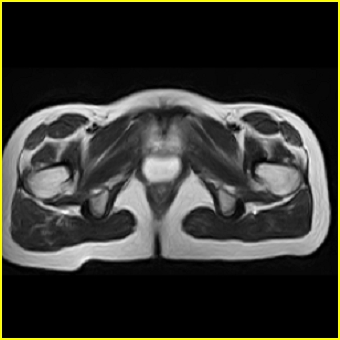

女、15岁、下腹疼痛2天,排尿困难1天。查体:处女膜闭锁,距处女膜约4至5cm处扪及一约5cm直径的圆形包块,张力较高,触痛明显、欠活动。b超提示子宫增大伴宫内增强回声团。

影像意见:子宫直肠陷凹积血。

更正影像意见:阴道积血。

处女膜闭锁,阴道积血

处女膜闭锁,阴道积血,子宫积血.

阴道积血,子宫积血.

子宫及阴道积血。

处女膜闭锁,伴子宫及阴道积血.